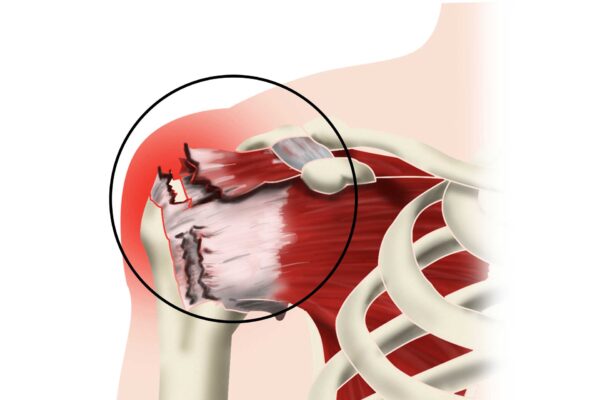

The best treatment for rotator cuff tendinopathies is a conservative approach composed of a medical component, mostly for pain relief, and a rehabilitation component to regain shoulder and full arm function.